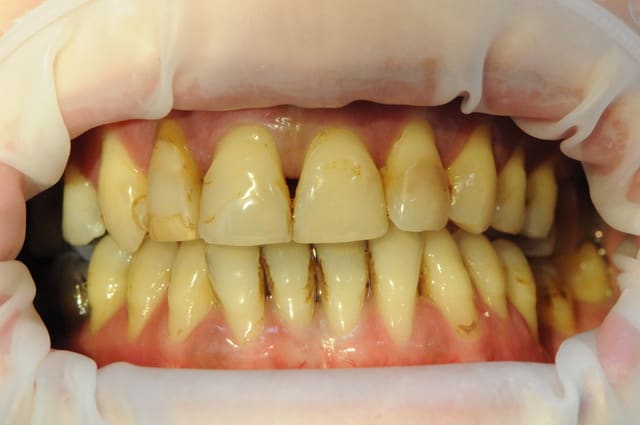

Jeune femme de 35 ans !

pas trop mal foutu au demeurant ( je sais, ça n'a rien à voir) et fumeuse de surcroit .

Ne découvre pas quand elle sourit.

Elle est venue consulter il y a 2 semaines en urgence pour mobilité et état infectieux sur 12.

La 12 est totalement perdue avec sa mobilité 3 sur l'échelle de Mhulmann, ce qui m'ennuie dans ce cas , c'est que le reste des dents, bien qu'étant fortement attaqué par la parodontite, ne soit que très faiblement mobile.

Là est donc mon dilemme; dois je tout extraire et planter à tout va (j'suis pas chaud) sachant qu'elle va perdre ses dents et le peu d'os qu'il lui reste si on temporise trop.

Ou bien, uniquement extraire et remplacer 12 par un implant qu'il sera ensuite plus difficile à intégrer avec les suivants.

Ou encore assurer le coté esthétique en retirant 12-11-21-22 et 2 implants au niveau de 12 et 22. puis gérer tranquillement le reste.

ce qui est sure, c'est que la 12 ne tiendra pas 3 mois de plus. Elle tient par l'opération du Saint Esprit et aussi par la contention que je lui ai faite.

A terme, dans tous les cas, tout va sauter!